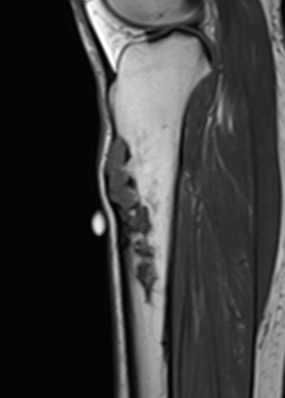

MRI

Khanna et al Skeletal Radiol 2008

- 24 cases of OFD / adamantinoma

- adamantinomas tend to be larger / cortical destruction / complete marrow involvement